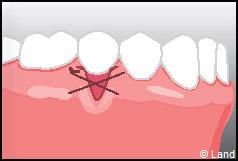

LES TECHNIQUES SANS APPORT DE GENCIVE :

Elles font appel à des lambeaux de gencive restante à proximité des récessions, qui sont déplacés et repositionnés sur la récession.